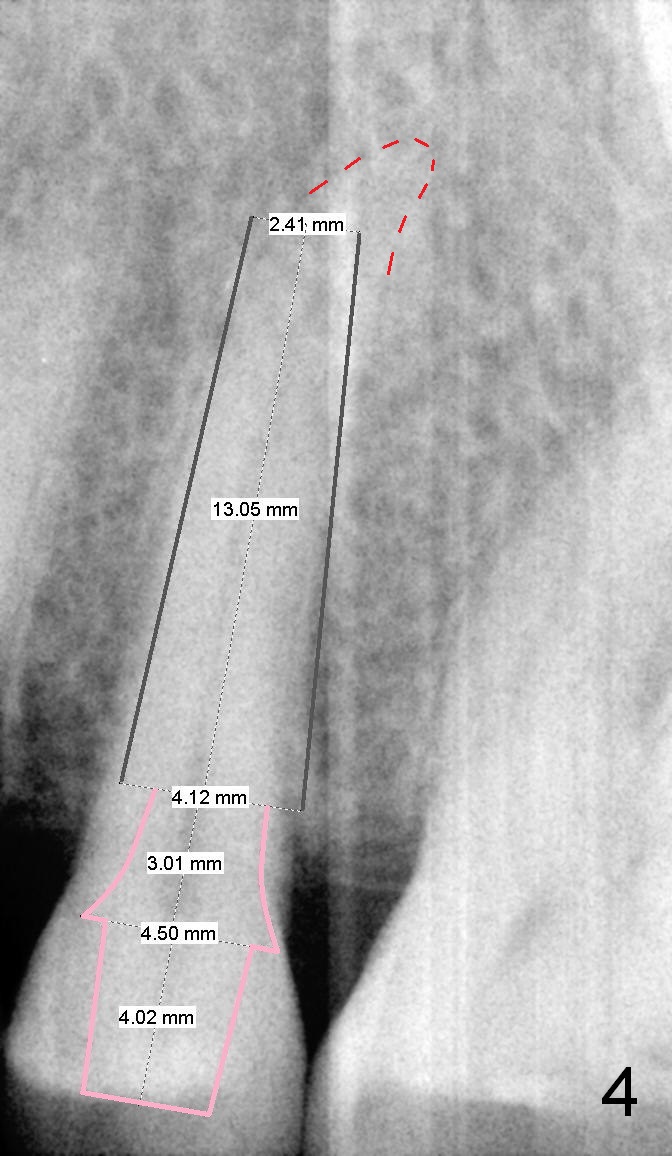

A 67-year-old lady (CC) has an implant at the site of #3, which replaces the fractured tooth (Fig.1). Recently the tooth #13 also fractures subgingivally (Fig.2). The tooth has a long and curved root. All of these suggest that the patient is a bruxer. The bone density is high. After extraction and placement of Clindamycin gauze in the socket, a 2 mm pilot drill is used to start osteotomy ~17 mm from the gingival margin, followed by 2.5 mm reamer ~ 17 mm, and 3 for 14 mm. If the socket looks small (mesiodistally), the goal is to place 4.1x14 (Fig.3) or 13 mm (Fig.4) implant. Otherwise use 4.5x17 mm Tatum tapered tap at 14 mm and plan to place a 4.5x13 or 14 mm implant. If it is difficult to insert an implant, use one size smaller drill from its original cassette or use 5x17 mm tap at 11 mm (to open up the entrance of the osteotomy). If the implant or tap is being deviated buccally while it is placed, use a Lindermann bur from Bicon Restorative plastic box to remove the bone from the palatal wall. When the side-cutting drill is cleaned, keep it in the Bicon Surgical Cassette. If the bone density turns out to be low, osteotomy depth will be 20 mm instead (Fig.5). When the flutes of 2.5 and 3 mm reamers collects bone particles, the bone density is high.